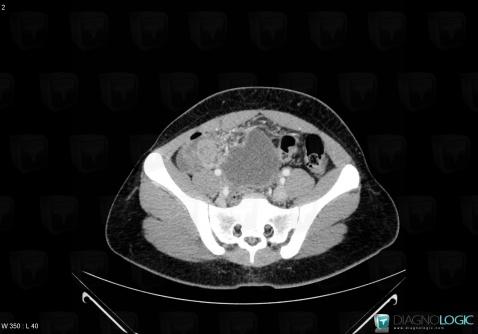

Tumeur-sac vitellin, Annexe / Ovaire - trompe, Pelvis / Périnée, Scanner

Voici les informations spécifiques à l'image clé ci dessus:

- Diagnostic Tumeur du sac vitellin, Localisation(s) Annexe / Ovaire - trompe, comportant les gammes Masse annexielle complexePelvis / Périnée, comportant les gammes Masse pelvienne complexe